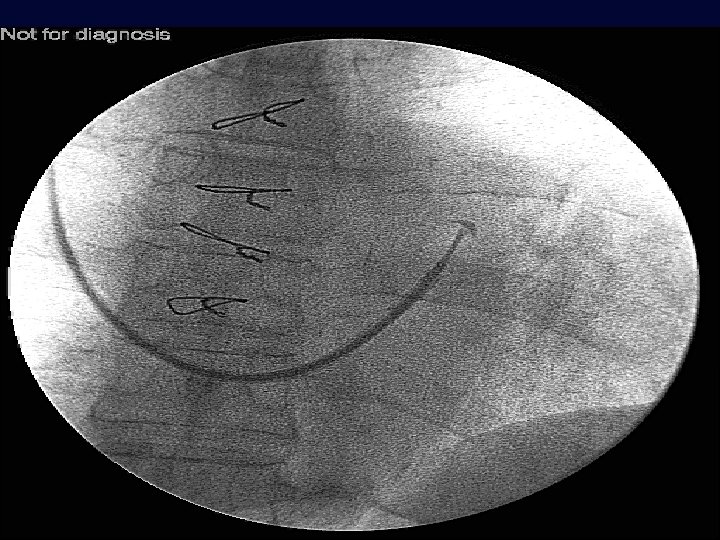

Venografia retrograda del seno coronarico Perforazione di piccola vena e impianto in v. poster-laterale OAS C D’Ascia, G Riccio Università degli Studi di Napoli Federico II

Venografia retrograda del seno coronarico v. ant Elettrodo in v. ant v. cm v. lat OAS C D’Ascia, G Riccio Università degli Studi di Napoli Federico II Posizionamento in Vena Interventricolare Anteriore

Vengrafia retrograda del seno coronarico Elettrodo in v. lat OAS C D’Ascia, G Riccio Università degli Studi di Napoli Federico II Posizionamento in Vena Laterale